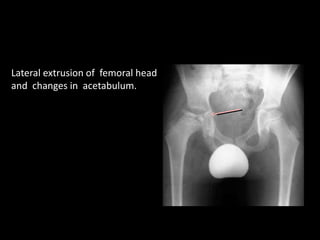

Lateral extrusion of femoral head

and changes in acetabulum.

BENJAMIN JOSEPH (JBJS 1989)

Osteoporosis of acetabular roof

Irregularity of contour

Premature fusion of triradiate cartilage (

bicomparmentalisation)

Hypertrophy of articular cartilage & changes in dimension

On plain xray -

bicompartmental

acetabulum appears to

be composed of 2 arc

partly overlapping each

other – interpreted as the

subluxated femoral head

articulating only with the

lateral half of the

acetabulum moulding it

into 2 compartments